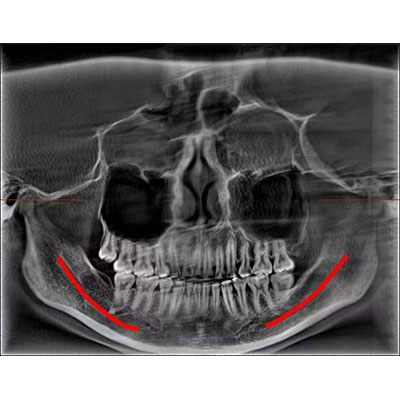

該款牙科CBCT產(chǎn)品采用動(dòng)態(tài)平板探測(cè)器,獲得三維圖像的同時(shí)還具有數(shù)字化全景功能,廣泛應(yīng)用于口腔頜面外科、正畸科、正頜外科、種植科、牙體科、顳下頜關(guān)節(jié)科等術(shù)前術(shù)后。

通過(guò)三維容積影像,提取高清口腔全景影像。

專有圖像校正技術(shù),去除金屬偽影,提高圖像分辨率。